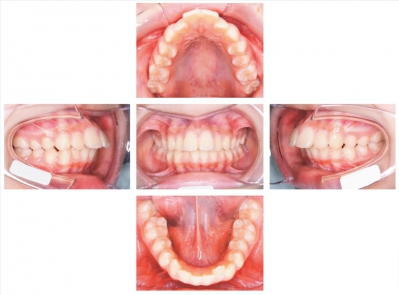

15歳の女子。口唇が閉じにくいことを主訴として来院した。永久前歯萌出後、咬み合わせに大きな変化はないという。11歳時に初潮を迎えたという。初診時の顔面写真、口腔内写真及び口腔模型の写真を別に示す。セファロ分析の結果を図に示す。

適切な治療目標はどれか。2つ選べ。